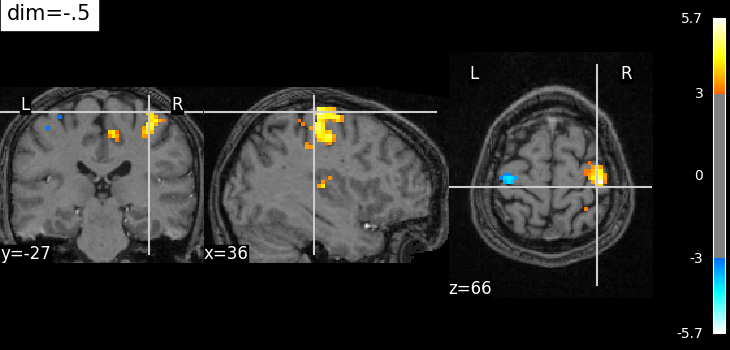

The dim argument controls the contrast of the background.

dim modifies the contrast of this image: dim=0 leaves the image unchanged, negative values of dim enhance it, and positive values decrease it (dim the background).

Plotting with enhancement of background image with dim=-.5¶

from nilearn import plotting

plotting.plot_stat_map(

localizer_tmap_filename,

bg_img=localizer_anat_filename,

cut_coords=(36, -27, 66),

threshold=3,

title="dim=-.5",

dim=-0.5,

)

<nilearn.plotting.displays._slicers.OrthoSlicer object at 0x7f3bd0b29d00>